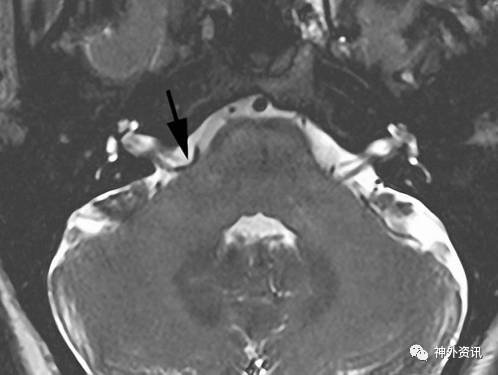

在准备进行微血管减压术(MVD)治疗面肌痉挛之前,应给予患者行头颅CT或高分辨率的后颅窝MRI来排除其他结构性病变。如果确实存在肿瘤,MRI可帮助术者术前了解肿瘤的边界(胆脂瘤,脑膜瘤等)以便进行术前准备。MRI T2加权序列可以显示出面神经REZ区域的异常血管扭曲。

如果面肌痉挛诊断确定,即使术前MRI未发现责任血管,笔者也建议进行手术探查。MRI的用处还在于可术前发现扭曲的椎动脉。由于扭曲的椎动脉在术中安全移动时难度往往较大,术者在术前应告知患者术后缓解率会因而降低。

图2. 轴位MRI T2加权显示面神经REZ区血管袢(箭头)压迫。